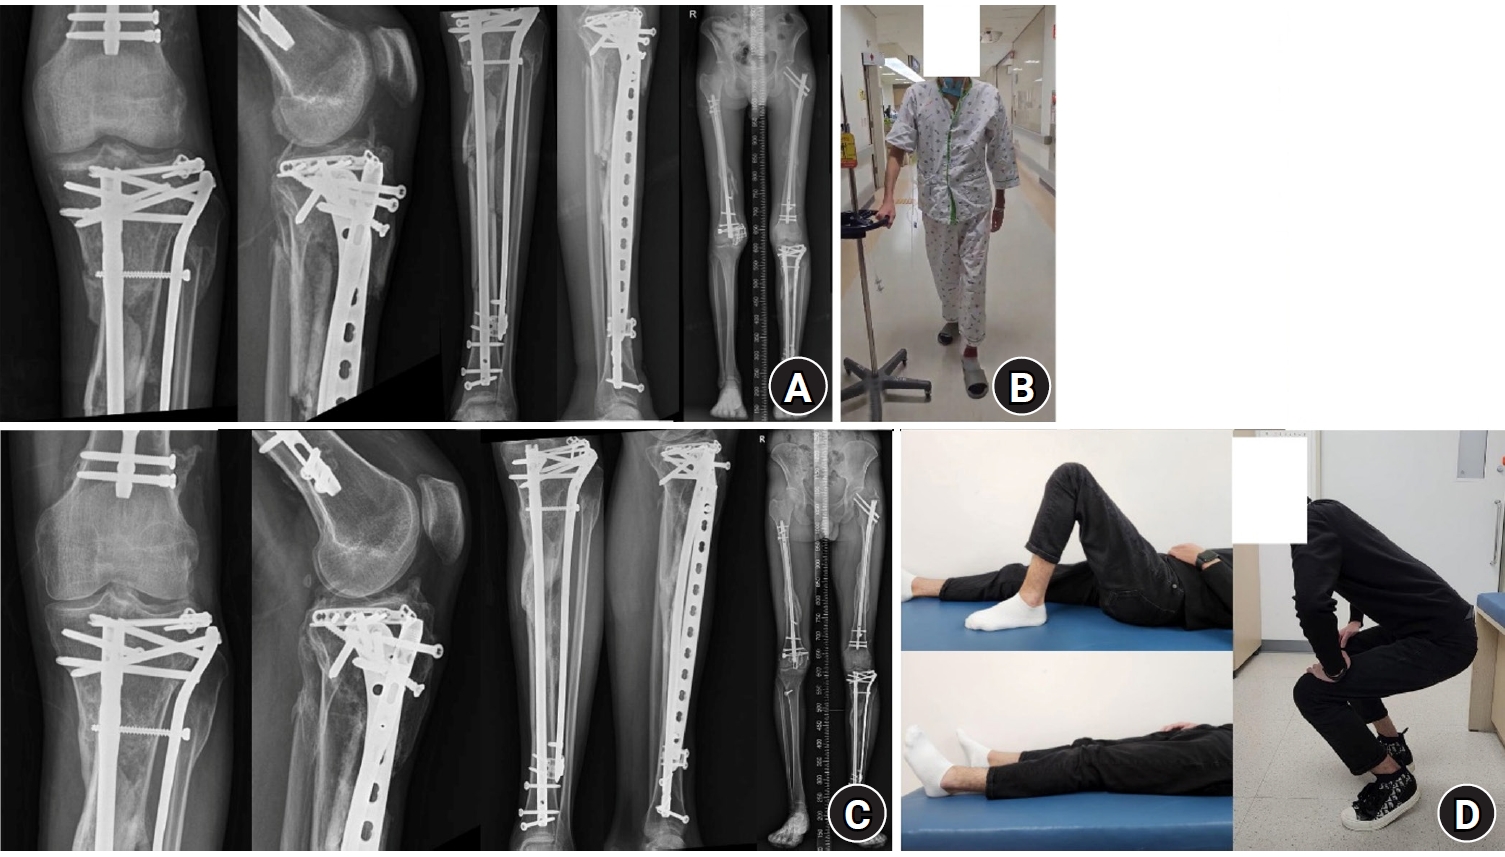

Fig. 4.

Follow-up plain radiographs and clinical photographs taken 6 weeks and 1 year after surgery. (A) Plain radiographs 6 weeks postoperatively. (B) Clinical photograph showing the patient ambulating with a walker 6 weeks after surgery. (C) Plain radiographs taken 1 year postoperatively. (D) Clinical photographs 1 year after surgery showing good knee joint range-of-motion and the ability to perform squatting exercises.

Fig. 4. Follow-up plain radiographs and clinical photographs taken 6 weeks and 1 year after surgery. (A) Plain radiographs 6 weeks postoperatively. (B) Clinical photograph showing the patient ambulating with a walker 6 weeks after surgery. (C) Plain radiographs taken 1 year postoperatively. (D) Clinical photographs 1 year after surgery showing good knee joint range-of-motion and the ability to perform squatting exercises.

Knee joint range-of-motion exercises were initiated immediately after surgery. Two weeks after surgery, the right tibial anteromedial open wounds had healed without complication. Assisted ambulation began 4 weeks after surgery, and by 6 weeks, the patient could ambulate independently with a walker, and fracture reduction was sustained in both lower limbs (Fig. 4A and 4B). Complete bone union was achieved for all fractures 6 months after surgery. The early initiation of rehabilitation helped the patient regain the ability to perform daily living activities, and at the 1-year follow-up, full functional recovery was confirmed (Fig. 4C and 4D).